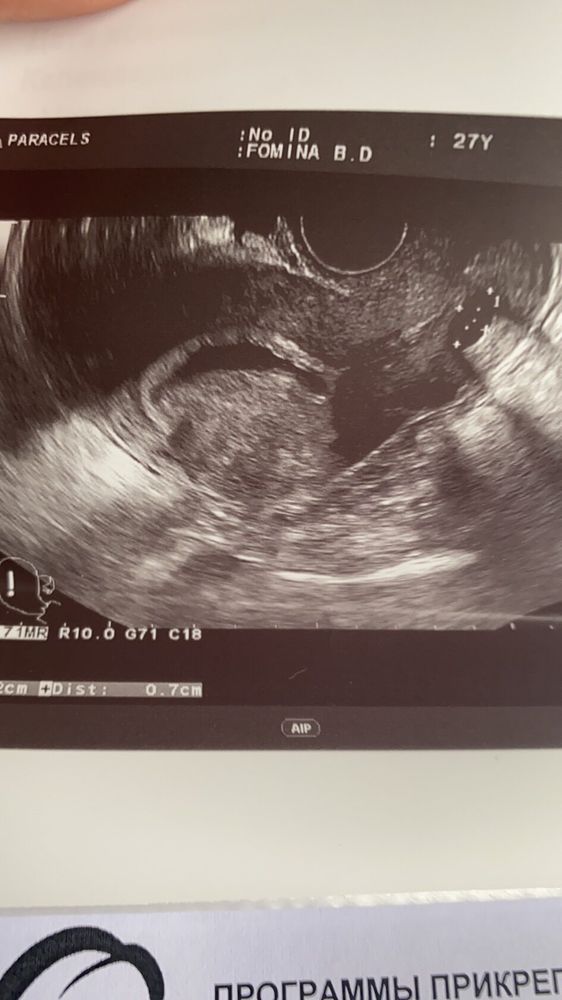

25 дпо узи

Сходила сегодня на узи, завтра ложусь в больницу((( Огромная гематома . Моя гинеколог говорит, что такое чувство что хотели начаться месячные , началась отслойка ( когда кровило на 12 и 13 дпо) , но мы их остановили . Так что я всегда за то, чтобы все-таки делать тесты до задержки , вот если бы я не узнала, что беременность есть, то просто бы подумала,что начались месячные . Без дюфа говорит мне тоже никак.

вот сдесь на фото сверху видно мою огромню гематому и справа снизу плодное яйцо